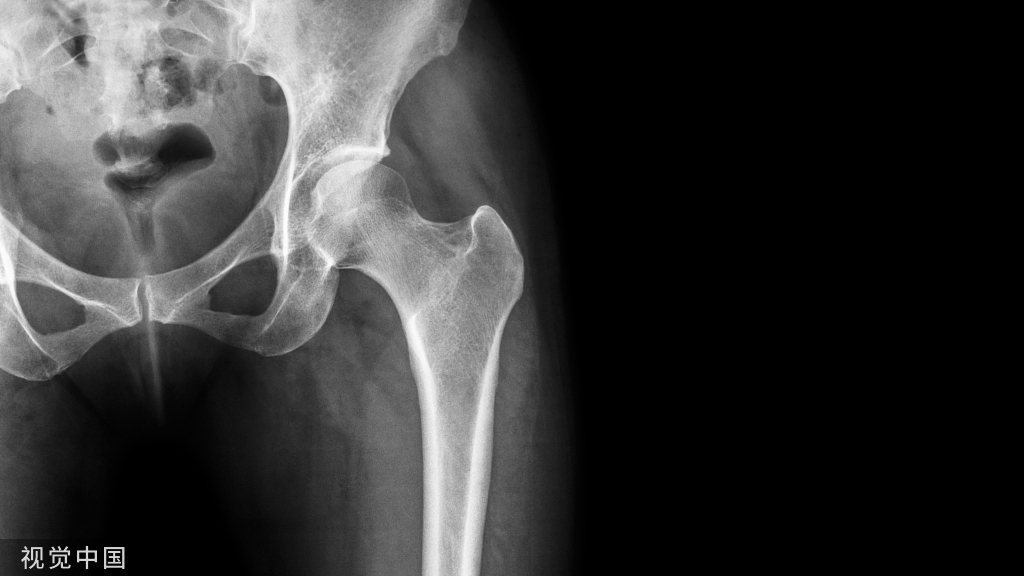

3.股骨颈环状透亮区,周边可见极薄硬化缘,为一常见现象,一般认为滑膜疝入皮质形成的皮质小坑,无临床意义(图3)。

图3 股骨颈环状透亮区,为滑膜疝入皮质形成的皮质下小坑,无临床意义